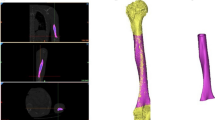

Using 3D Slicer software, the previously obtained CT image data was transformed into a finite element model of the left femur. Osteotomy was used to cut and reshape the bone in this 3D virtual patient model, and the angle between the femoral head and femur was corrected to 126°, as shown in Fig. 1a [24].

In addition, the pediatric hip locking plate (LCP Pediatric Plate System, DePuy Synthes company, USA), used in this 3D virtual patient model, was measured using a digital caliper and converted to a finite element model, as shown in Fig. 1b. The screw holes in this pediatric hip locking plate were set to a diameter of 5.0 mm, and the location and number of screw holes were set to three in the direction of the femoral head and three in the direction of the femur. Based on the product specifications, the diameter and length of the screws were set to 5.0 mm and 23–45 mm, respectively. After selecting the positions of the screws inserted into the femoral head, the screws inserted in the direction of the femur were positioned based on the groove of the pediatric hip locking plate, and they were vertically fixed with the pediatric hip locking plate. Finally, ABAQUS (Version 2022, Dassault Systemes, Simulia, USA) finite element program was used to perform three-dimensional FEA, with a total of 1,496,941 solid elements in the finite element model. The femur and pediatric hip locking plate were composed of C3D4 element types in the form of tetrahedrons of sizes 0.2 and 0.5 mm, respectively, whereas the screw was composed of C3D8R element types in the form of hexahedrons of size 0.3 mm.